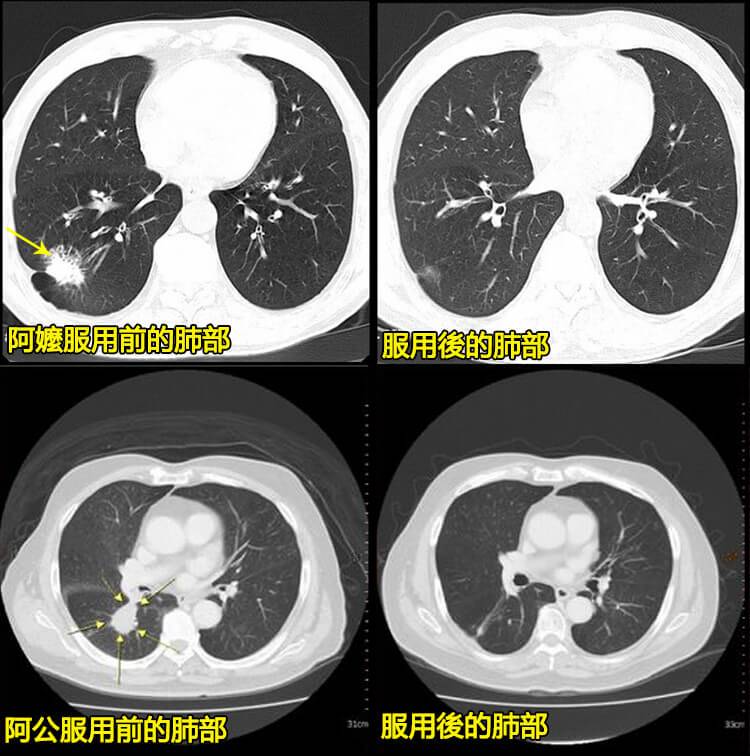

我家75歲的阿嬤是個老哮喘患者,最開始吃西藥也能控制住,但就是不能乾重活不然咳喘的特別厲害。可一遇到變天或感冒阿嬤就咳得特別厲害、胸口憋得難受接不上氣;晚上睡覺不能平臥血壓還忽高忽低。去年夏天,阿嬤從報導上瞭解到(橘紅顆粒)是專業止咳平喘的中藥丸安全無副作用。且還有夏治咳喘冬不再犯的優勢,她當即就購買了3階段。效果可真明顯,阿嬤服用當天咳嗽明顯減少;氣管很舒暢;連續服用3個階段後不再有胸悶、心慌的感覺,不咳不喘,肺功能也恢復正常了血壓也平穩了。還有我的阿公是個老煙民了,經常咳嗽、吐痰看到阿嬤服用(橘紅顆粒)有效果後現在也用上了,服用後,阿公也沒再咳嗽了。